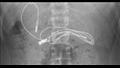

نقل أحد المراهقين الذي يبلغ من العمر 15 عامًا، إلى المستشفى في تركيا، بسبب الشعور بألم شديد في معدته والرغبة في الغثيان، مما استدعى إلى تشخيصه من خلال إجراء أشعة مقطعية على البطن.

وظهرت نتيجة الأشعة وجود شيء يشبه الثعبان في البطن، و تبين أنه سلك شاحن طوله 90 سم، ما استدعى إجراء عملية جراحية طارئة لإستخراج السلك من المعدة، وخلال العملية ظهرت ربطة شعر، وذلك وفقًا لما ذكره موقع "the mirror" البريطانية.

وذكر الأطباء أن تلك الجراحة تعد معقدة للغاية، بسبب مرور أحد أطراف السلك إلى الأمعاء الدقيقة، ولكنه سرعان ما تعافى الطفل و عاد إلى منزله، مع العلم أن الحالات التي تقوم بابتلاع أشياء غريبة تنتشر بين العديد من الأطفال والمراهقين.